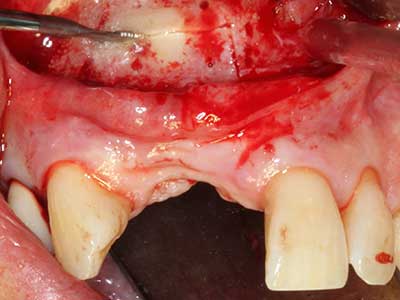

Marginal periodontal diseases are the main reason for extractions in advanced age. These diseases are primarily caused by bacterial colonization of the gingival pocket, which causes inflammation followed by loss of the periodontium. The formation of subgingival biofilms and concrements is a significant aetiological factor for marginal bone atrophy, so their removal is an important part of the treatment (Drisko 2014, Plessas 2014).

Initial and surgical treatment phases are differentiated in the treatment of marginal periodontitis. In addition to instruction in oral hygiene and motivating patients, both phases should include adequate cleaning of the root surface. In the regenerative setting an open access is generally preferred. The root surface can be cleaned by piezo surgery using special attachments, where instruments with different curvatures are used to reach areas that are difficult to access, such as furcations. The integrated irrigation in the system flushes the detached concrements and bacteria out of the pocket. Specialized systems such as the Piezomed also include application feedback to minimize the ablation of hard dental substance. The greater the pressure on the periodontal attachment the greater the reduction in the amount of ablation.